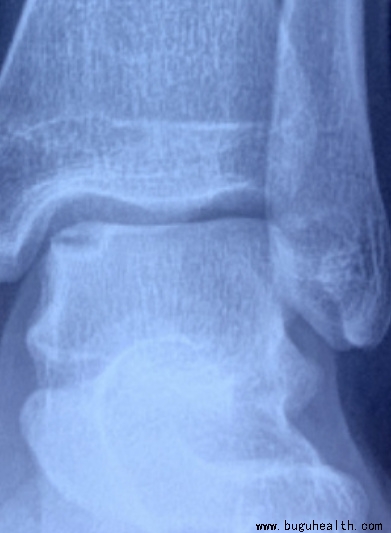

- 布骨医学科普:反复崴脚,可不是什么小事 BuGuRMC布骨康复医疗中心 ,2023-05-04

- 不小心崴了一脚,大多数人的处理办法是简单抹点药、热水泡泡脚、多走走路,认为这样就能好,很少想到去医院看。其实,轻度的踝扭伤,不看医生可能没什么大问题,但一些严重扭伤的情况,如果不当回事,拖着不去医院,最后可能不得不上手术台。这不是故意耸人听闻, 有研究指出在需做「踝关节融合和人工踝关节置换手术」的患.....